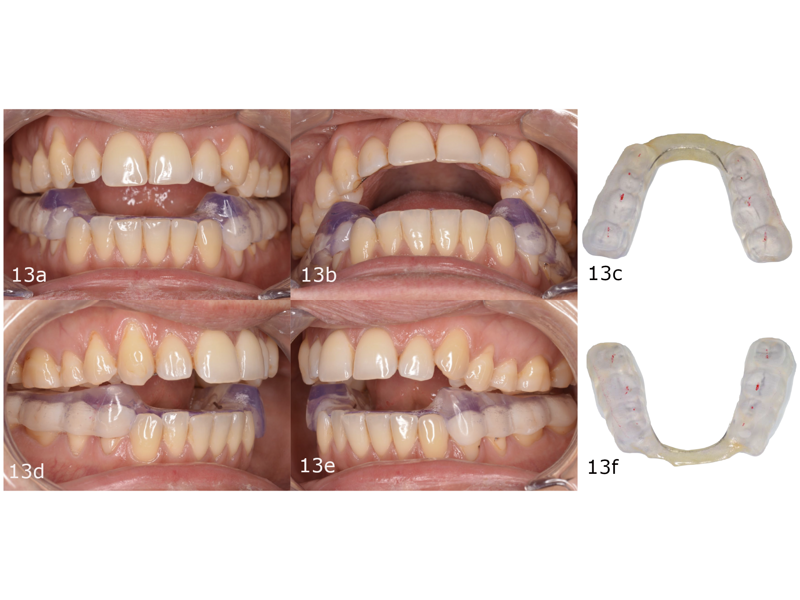

After four months of wearing the splint, the patient’s condylar position was stable (Fig. 13). This position was maintained during treatment in order to retain the true arc of closure by placing occlusal build-ups on the posterior teeth (Figs. 14 & 15). These occlusal build-ups also have an intrusion effect, favouring the correction of patients who require vertical control. Only when the patient is stable do we have a predictable situation for planning and starting orthodontic treatment. In treatment with aligners, planning based on the patient’s true arc of closure allows us to achieve successful results in less treatment time and with fewer aligners and fewer refinements while protecting the TMJ.